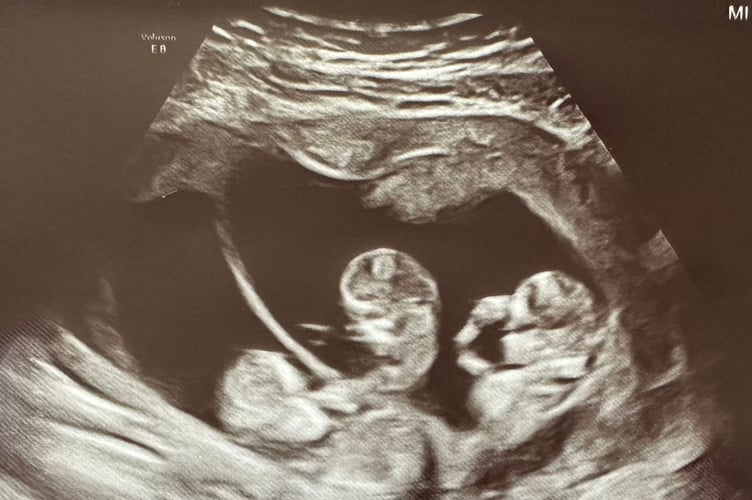

At eight weeks, the couple decided to have a private scan as Hannah's parents were visiting and they wanted to tell them in person that they were going to be grandparents.

During the scan, the sonographer's hands started to shake and Hannah and Chris immediately thought the worst but she revealed the pair were expecting triplets.

Hannah said: "We didn't know what to expect at the scan - it felt like the specialist was taking ages.

"When the sonographer stopped she turned to us and she was shaking, we were expecting bad news.

"She had never been in the position before that she found triplets, it was a big moment for her and an even bigger moment for us.

"I had a nervous laugh, I started laughing right away. She turned to the screen and pointed out the different places where the babies were.

"I burst out crying, there were a lot of emotions."